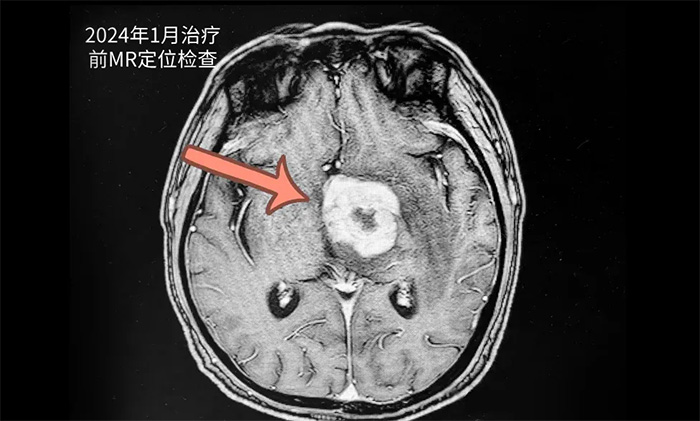

患者秦某(化名)73岁,男性。2023年12月无明显诱因出现头晕、头痛,伴言语不清。于当年12月21日在当地医院就诊,完善相关检查MRI示颅内占位性病变,颅内病灶穿刺活检病理提示:高侵袭性B细胞淋巴瘤。后患者来到上海蓝十字脑科医院寻求进一步治疗。

▲ 治疗前影像

王晓东主任团队为患者完善各项检查。根据患者的临床资料、病理诊断和影像结果,明确患者满足放疗条件,并制定了完善周密的放疗计划。为患者开展20次放射治疗。历时约1个月完成治疗后,患者头晕、头痛,伴言语不清等症状有了不同程度改善。复查头颅MR,可见病灶范围明显缩小。